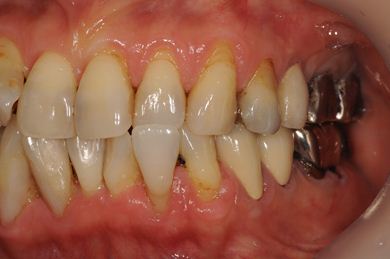

抜歯即日スピードインプラント+セラミック治療

| 治療内容 | インプラント2本(抜歯即日スピードインプラント)、ハイブリッドセラミッククラウン5本(セラミック用土台2本)、ハイブリッドセラミックインレー1本 | ||||||||||||||||||||||||||||||||